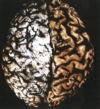

Figura 28.36 Enfermedad de **Alzheimer** con atrofia cortical más notoria en la derecha, donde se han extirpado las meninges.

Atrofia difusa Estrechamiento de las circunvoluciones Ensanchamiento de los surcos Hidrocefalia ex vacuo (no se ve) - dilatación ventricular compensadora